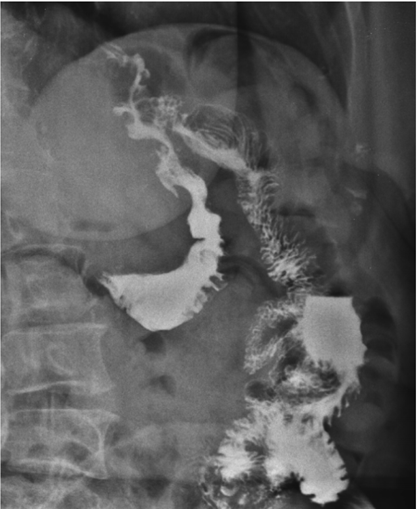

Mulher de 55 anos, submetida à cirurgia bariátrica há 6 meses sob técnica de bypass gástrico em Y de Roux, queixa-se de desconforto epigástrico e de dores intermitentes no abdome superior há 3 meses, sendo solicitado pelo médico cirurgião exame contrastado do esôfago-estômago-duodeno, representado pelas duas imagens abaixo. Obs.: contraste administrado por via oral.

Diante do exposto acima, analise as afirmativas abaixo e assinale a alternativa correta.

I. Há refluxo de contraste da via alimentar para a via biliopancreática por incompetência da anastomose terminolateral jejuno-jejunal.

II. Os achados evidenciam a presença de fístula entre a anastomose bolsa gástrica-alça jejunal e o estômago excluído.

III. Observa-se extravasamento de meio de contraste para a cavidade abdominal, achado suspeito para deiscência da anastomose bolsa gástrica-alça jejunal.